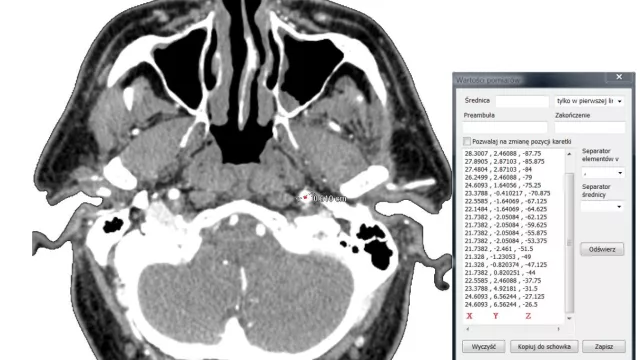

Wyznaczenie trajektorii naczyń

mat. autora

Jedną z przyczyn migrenowego bólu głowy, zawrotów czy omdleń mogą być problemy z niedokrwieniem mózgu. Do diagnostyki lekarze wykorzystują ultrasonografię dopplerowską lub tomografię komputerową. Zalety obu metod łączy zastosowanie narzędzi do modelowania przestrzennego oraz numerycznej mechaniki płynów opracowane w Instytucie Maszyn Przepływowych.